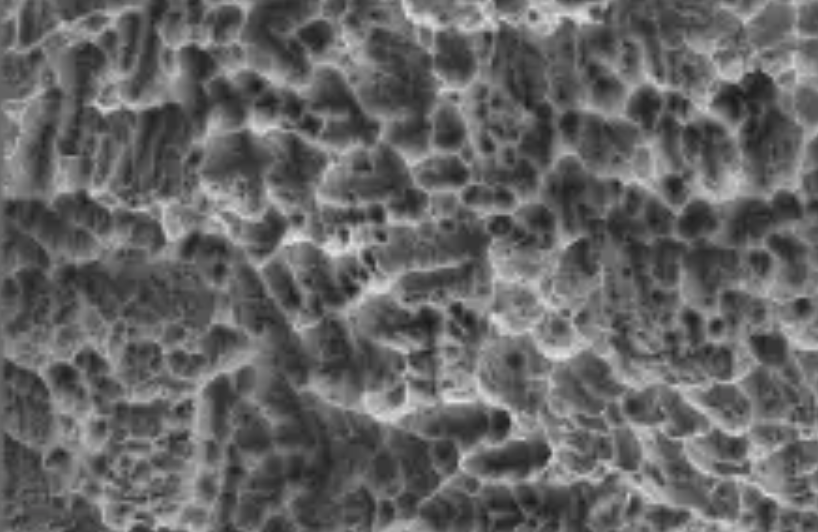

S.L.A. Surface

우수한 S.L.A. SURFACE 표면처리로

골과의 반응이 우수합니다.